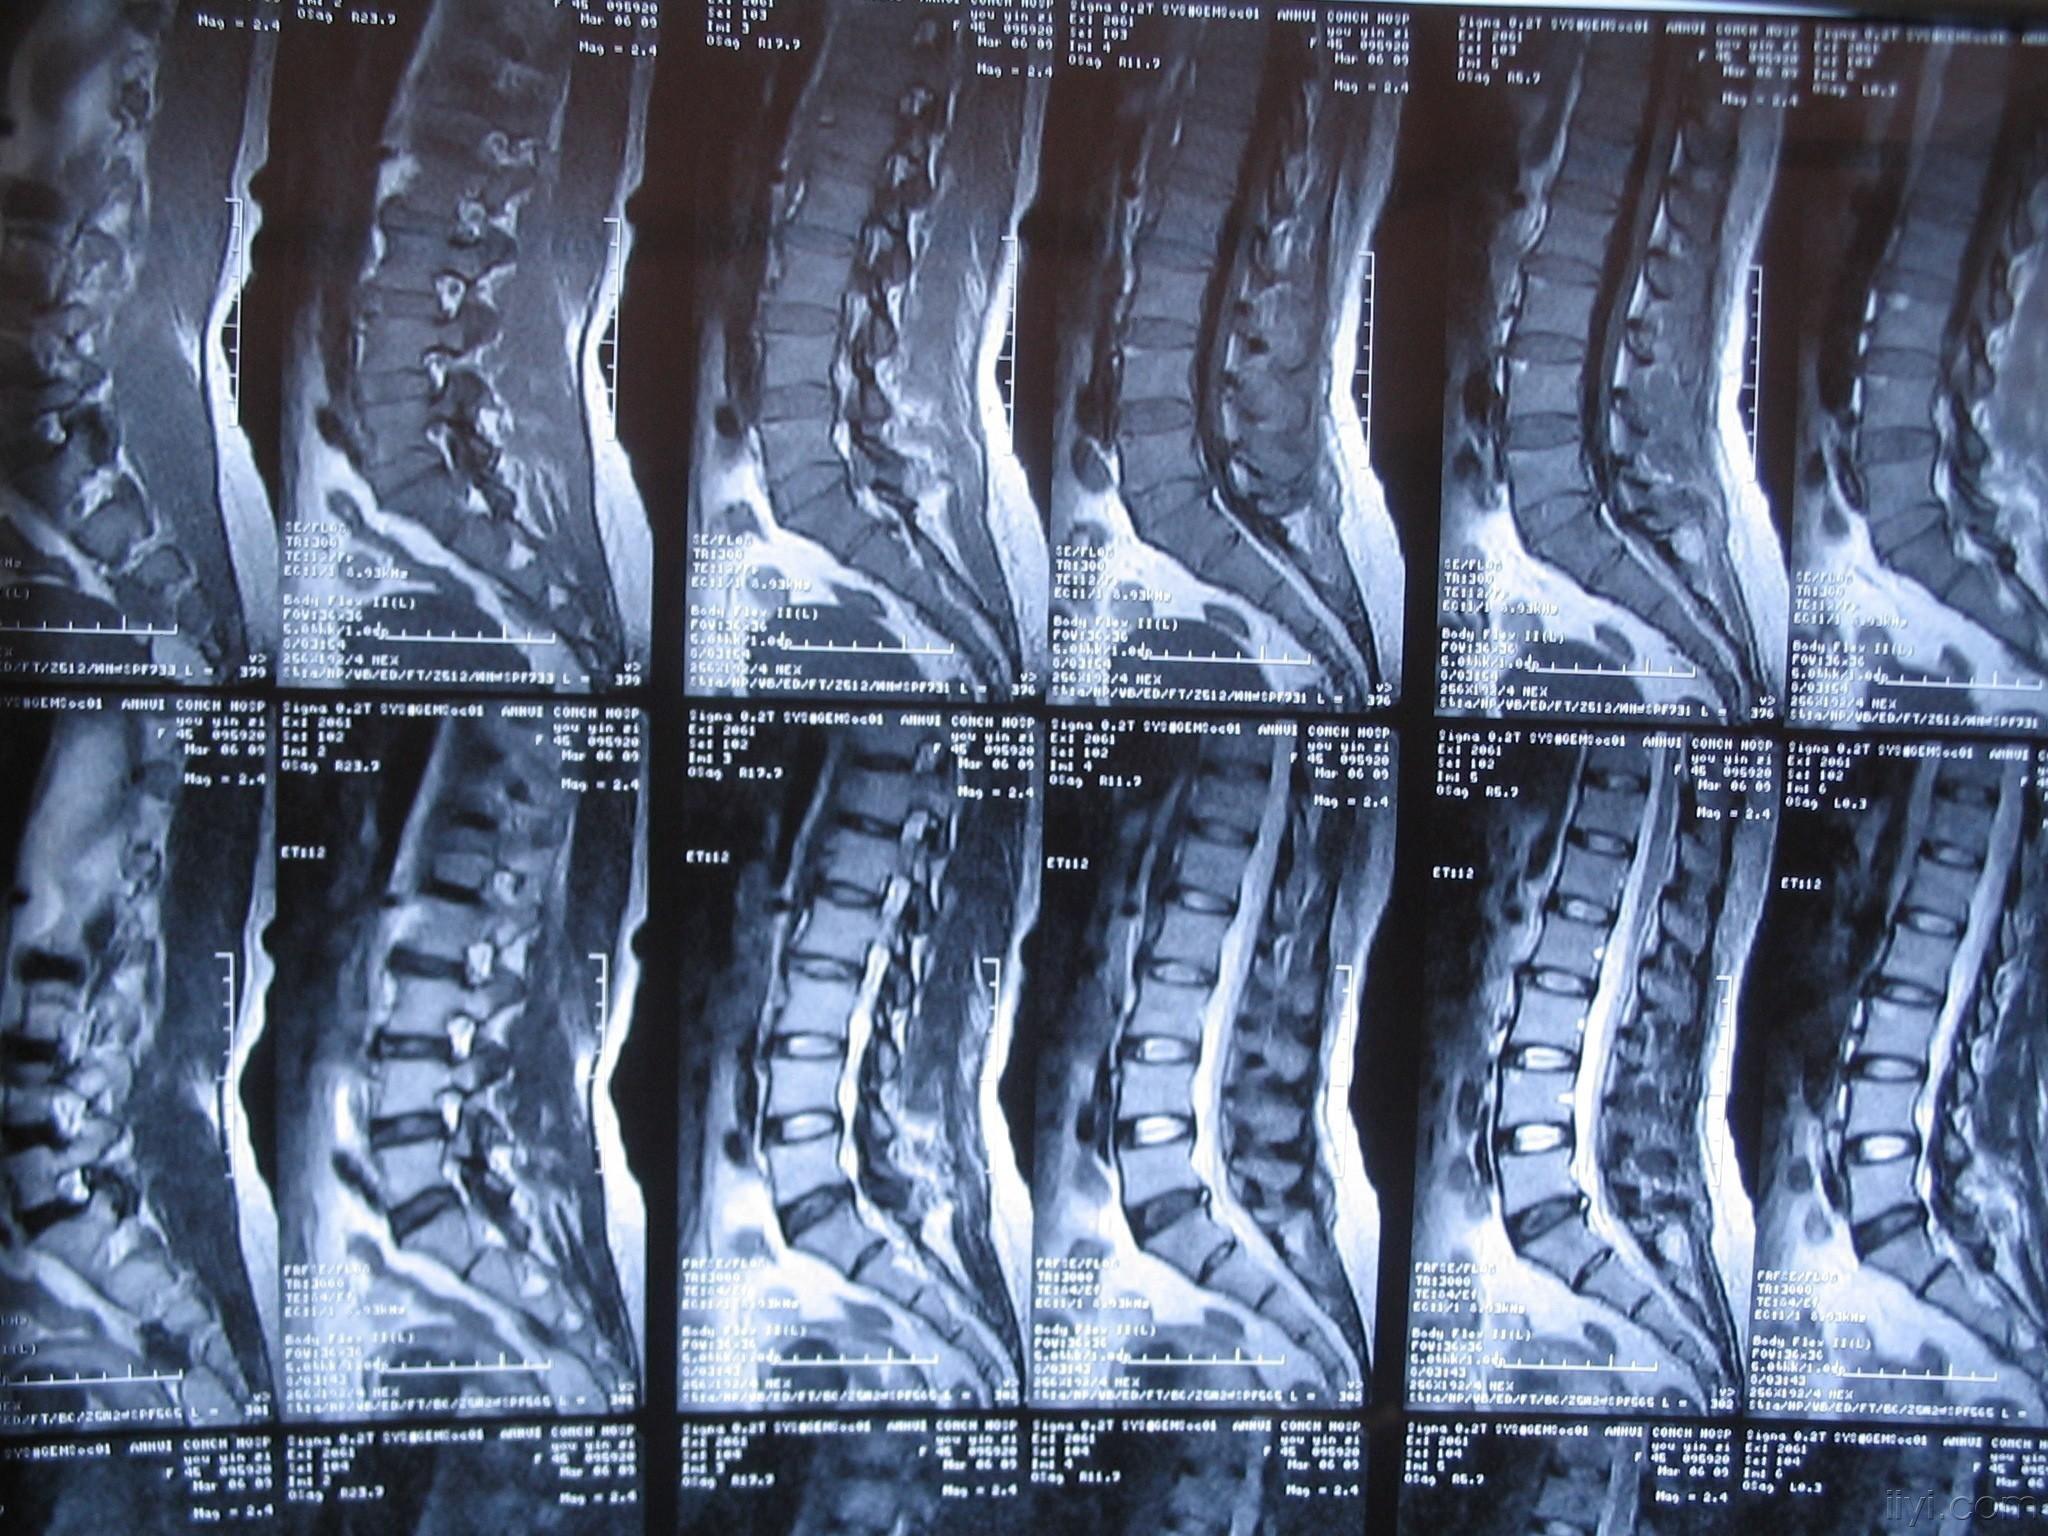

2019-5-24晚18:00时完成一例l3/4,l4/5椎间盘

请教我读张腰椎ct片